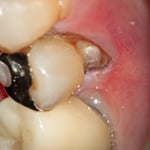

左 :歯の根元に生じた虫歯です。(茶色の部分)この状態では、どこまでが歯なのか歯肉に覆われていてわかりません。通常、このままプラスティックを充填してしまうことが多いようです。